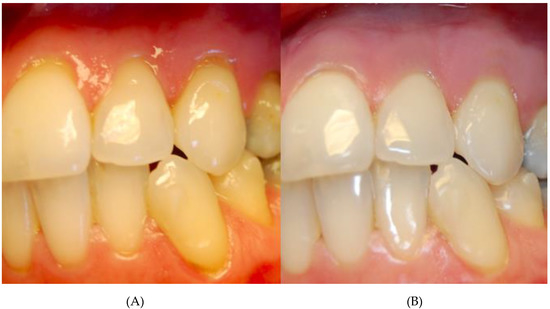

| Before Collagen Injection | After Two Collagen Injections | p | |

|---|---|---|---|

| Recession high | 1 (0.5–2) | 0 (0–0.5) | <0.000001 |

| Papillae loss | 1 (0.5–1.5) | 0 (0–0.5) | <0.000001 |

| Thickness of gingiva | 0.3 (0.1–0.5) | 0.6 (0.3–0.8) | <0.000001 |

| Before Collagen Injection | After Three Collagen Injections | p | |

| Recession high | 0.5 (0–1.5) | 0 (0) | 0.00002 |

| Papillae loss | 1 (0.5–1.5) | 0 (0) | 0.00001 |

| Thickness of gingiva | 0.1 (0.1–0.4) | 0.7 (0.5–1) | 0.000002 |

| After Two Collagen Injections | After Three Collagen Injections | p | |

| Recession high | 0 (0–0.5) | 0 (0) | 0.02 |

| Papillae loss | 0 (0–0.5) | 0 (0) | 0.1 |

| Thickness of gingiva | 0.5 (0.3–0.6) | 0.7 (0.5–1) | 0.000004 |